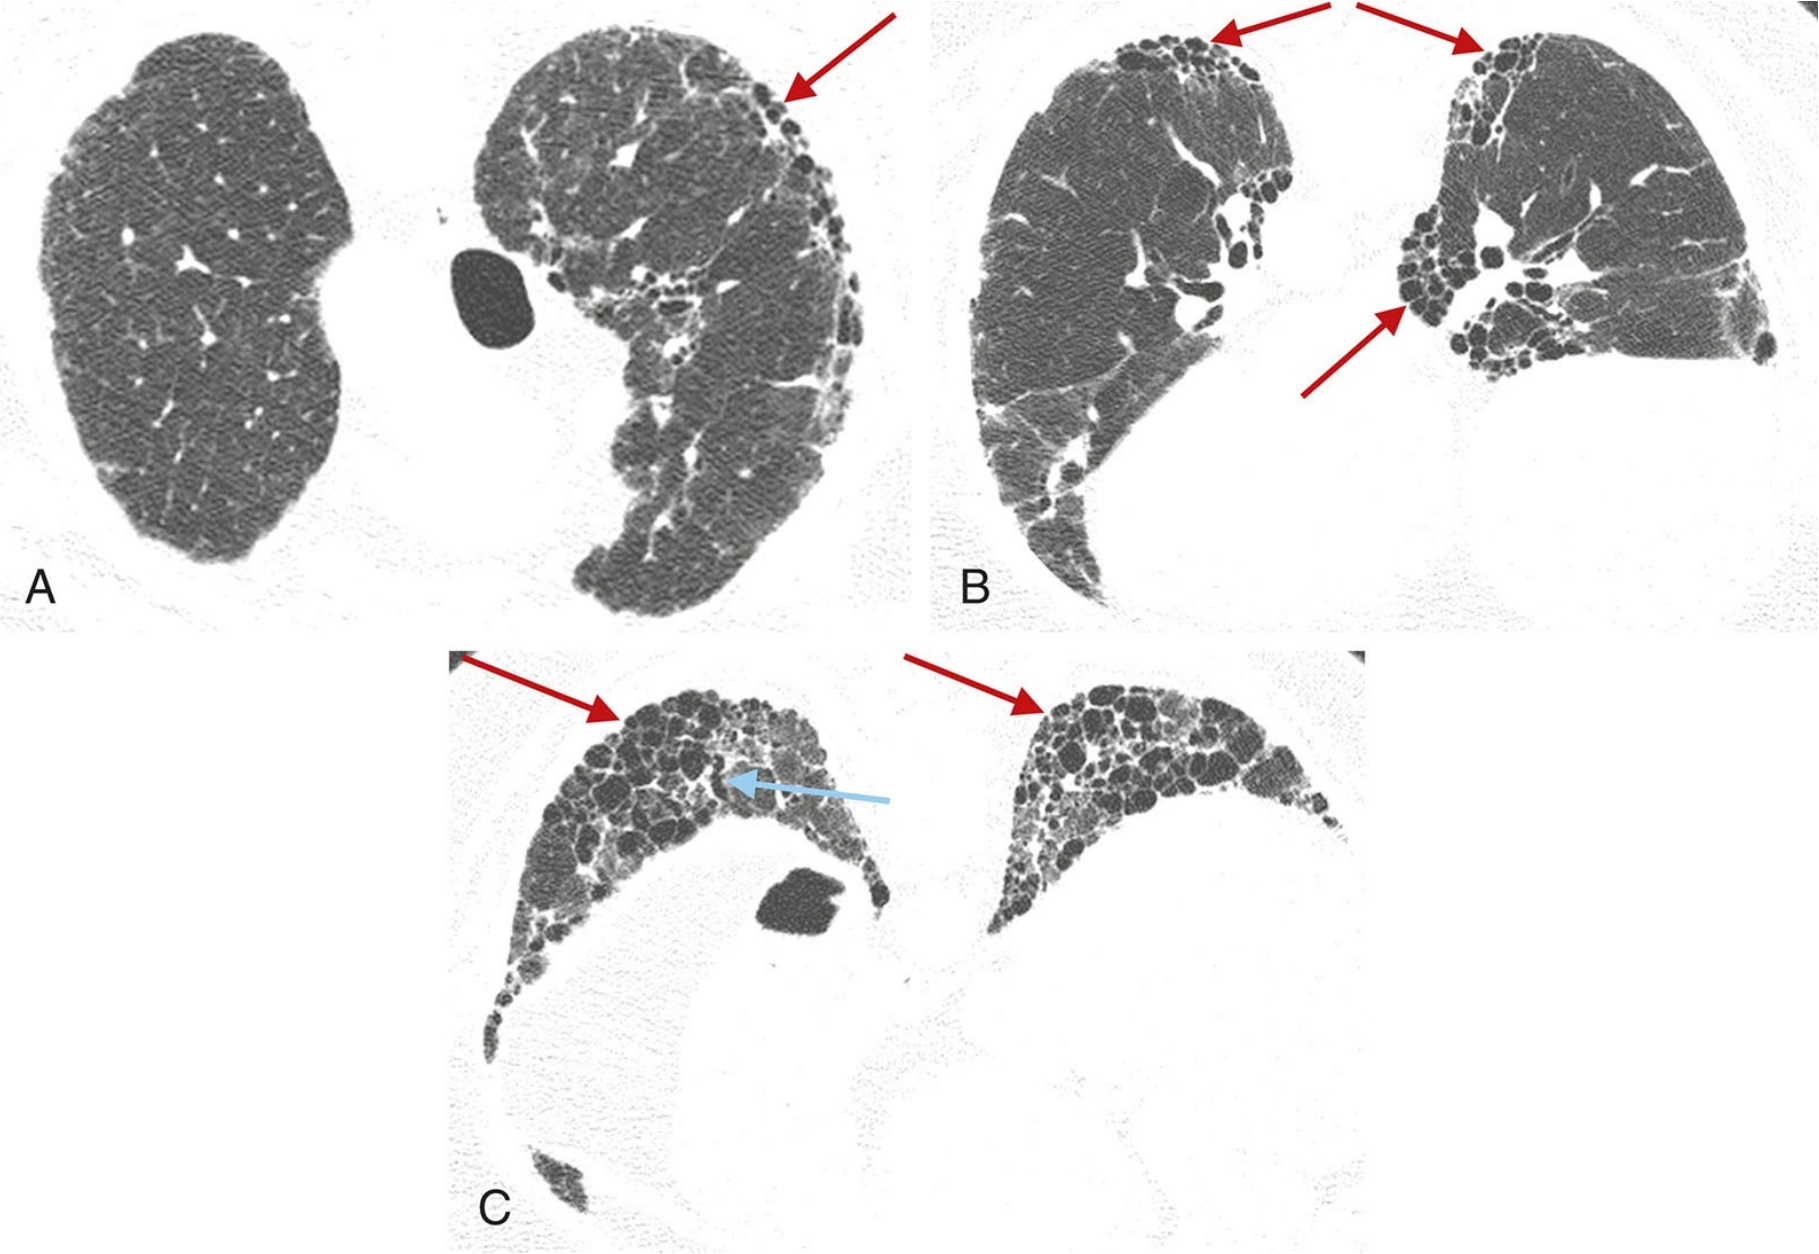

ffd7bb23e755e95335b0c12dc29c866a.png

普通型间质性肺炎(UIP)的典型表现。

A.伴有特发性肺纤维化的UIP模式患者,HRCT显示广泛的胸膜下和肺基底分布为主的蜂窝征;

B.散在分布的胸膜下蜂窝征(红箭),与相对正常的肺组织(蓝箭)相间;

C.俯卧位HRCT显示UIP患者的蜂窝征(箭),可为单层(黄箭)或多层(蓝箭);

D.早期UIP表现为轻度的胸膜下网状影和蜂窝征,虽然程度轻微,但仍可明确判定蜂窝征(箭)。